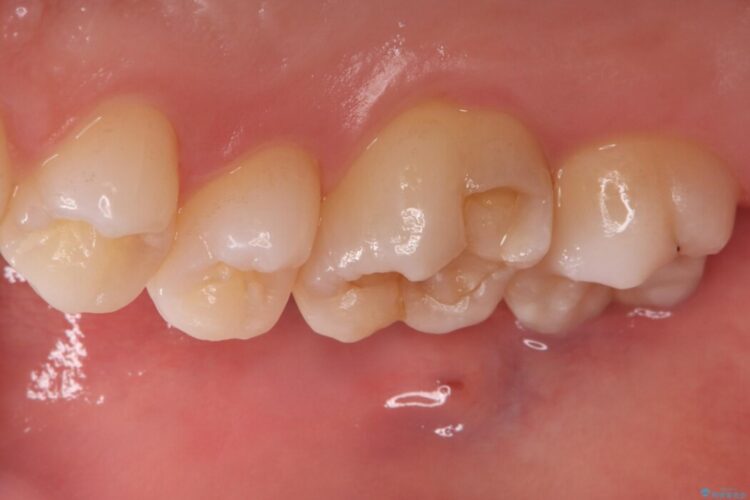

右上奥歯が欠けてしまい来院されました。

右上6番の舌側が欠けてしまっている状態でした。

破折リスクを考慮し、セラミックアンレーで治療を行うこととしました。